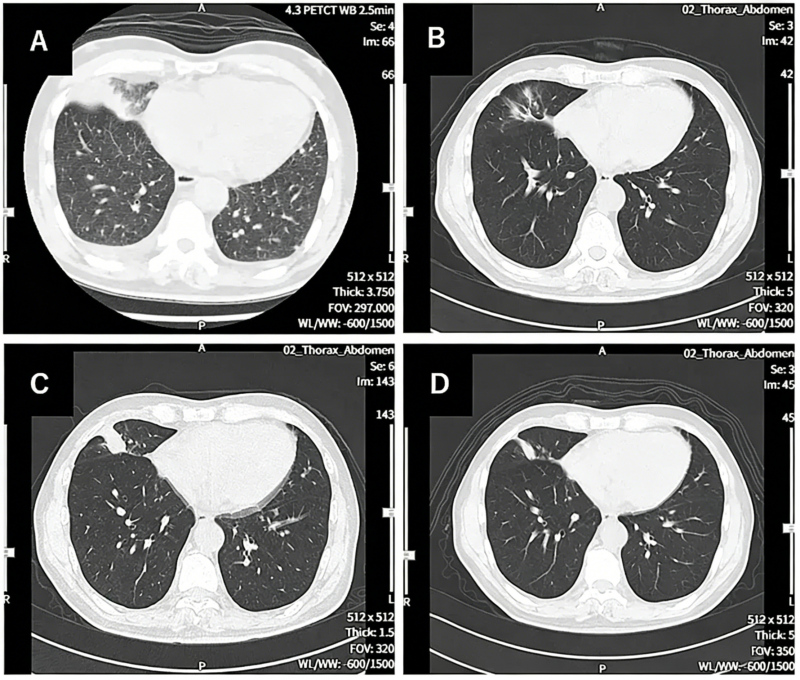

其中一位69岁的晚期非小细胞肺癌患者,经历了多线治疗失败,但在接受3个周期的联合治疗后,右肺的原发病灶基本消失,左肺和纵隔淋巴结的转移灶也显著退缩,达到了临床上的“部分缓解(PR)”。整个过程仅仅出现轻微发热等可控反应。这对于一个终末期患者而言,无异于绝处逢生。